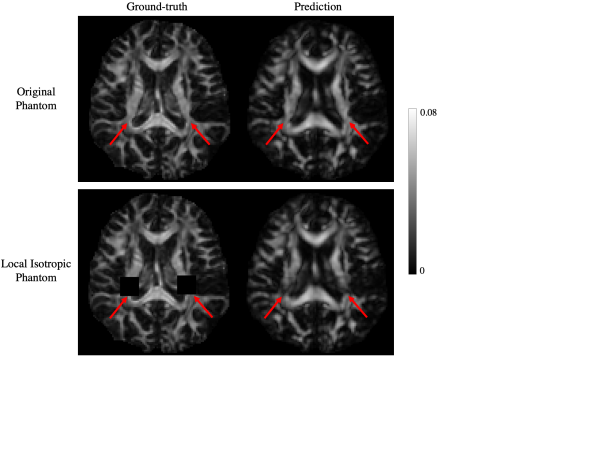

To better understand the contribution of the learned prior to the reconstructed MSA of DeepSTI, we tested DeepSTI on simulated phase generated from a fully isotropic STI brain phantom (manually set MSA=0 across the whole brain). Furthermore, to mimic the more realistic case of partially isotropic regions caused by lesions, we also tested our method on a local isotropic phantom where two cubic isotropic regions of size (10voxel)3superscript10voxel3(10~{}\text{voxel})^{3} were inserted in the original anisotropic phantom (Fig. 10).

Fig. 9(a) shows the histogram of MSA values predicted by DeepSTI in major fiber regions (defined by voxels with ground-truth MSA >>0.02 ppm) for the original anisotropic phantom and the fully isotropic phantom, while Fig. 9(b) shows corresponding MSA maps. Although DeepSTI naturally does not predict exactly zero MSA for the isotropic phantom, it is clear that the MSA values predicted by DeepSTI are significantly smaller in the isotropic phantom than in the original phantom. Fig. 10 depicts the MSA maps predicted by DeepSTI for the local isotropic phantom, where a notable decrease in anisotropy can be observed in DeepSTI’s prediction for both of the manually-defined isotropic local regions (indicated by red arrows).

Refer to caption

Figure 10: DeepSTI prediction for a locally isotropic brain phantom, in comparison with the corresponding prediction for the original anisotropic phantom. Top row: ground-truth MSA (left) and DeepSTI-predicted MSA (right) for the original anisotropic phantom. Bottom row: ground-truth MSA (left) and DeepSTI-predicted MSA (right) for the locally isotropic phantom with two manually selected isotropic regions (indicated by red arrows).

Fig. 9 presents the results on an unrealistic but interesting case, where reconstruction of a completely isotropic brain phantom is attempted. Although the results indeed show decreased MSA in white matter areas compared to the anisotropic phantom, the predicted anisotropy values are not completely zero. This is expected, because the solution given by DeepSTI can be broadly regarded as a maximum a posteriori (MAP) estimate for the ill-posed STI reconstruction problem, maximizing the probability of the solution under the learned prior from data. A completely isotropic brain has probability zero in the distribution of human STI (and, by extension, in all the training data used to train the model) and thus a completely isotropic reconstruction should never be expected. Yet, this does not mean that regions of abnormal anisotropy, or areas that are mostly isotropic in white matter, could not be approximately reconstructed. On the contrary, this is demonstrated by the experiment with the locally-isotropic regions in Fig. 10, as well as by the results on the MS patients.